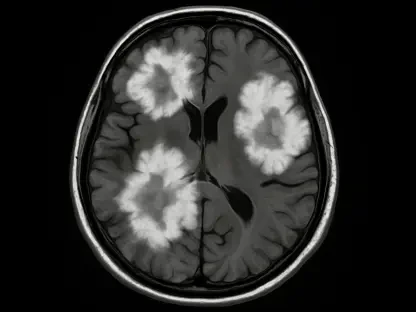

At the heart of Medtronic’s financial upswing lies its cardiovascular portfolio, which delivered an unprecedented $3.44 billion in revenue for Q2 FY26, marking a 10.8% increase from the prior year. This represents the strongest growth in this segment in over a decade, driven predominantly by the pulsed-field ablation (PFA) franchise. The PFA technology, designed to treat abnormal heart rhythms with enhanced safety and efficacy, reported a staggering 71% growth rate in the quarter, accelerating from nearly 50% in the previous one. Key products like the PulseSelect PFA system and the recently FDA-approved Sphere-9 Dual Energy Catheter with Affera Mapping System have been instrumental in this surge. Notably, the US market alone saw over 300% growth, complemented by significant gains internationally, highlighting the global appeal and clinical acceptance of these innovations.

The success of the cardiovascular segment extends beyond mere revenue figures; it reflects Medtronic’s strategic emphasis on addressing critical healthcare needs through cutting-edge solutions. The PFA franchise’s rapid adoption by clinicians stems from its ability to offer a safer alternative to traditional ablation methods, minimizing risks to patients while improving outcomes. This technological edge has not only bolstered Medtronic’s reputation as an innovator but also expanded its market share in a segment where demand continues to rise. The FDA approvals of key PFA products in recent years have further accelerated this momentum, providing regulatory validation that enhances trust among healthcare providers. As cardiovascular diseases remain a leading global health concern, Medtronic’s focus on this area positions it to meet escalating demand with solutions that are both effective and accessible across diverse markets.